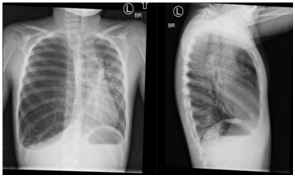

Figure 3 CT Chest coronal planes-lung and soft tissue windows.

Figure 4 CT Chest lung windows.

Physical examination was notable for tachypnea with a maximal respiratory rate of 48 breaths per minute, tachycardia, pulse oximetry (SpO2) of 92%, diminished air exchange at right chest with asymmetric barrel chest (right > left) including increased anteroposterior diameter. Flexible fiberoptic bronchoscopy with bronchoalveolar lavage (FFB BAL) demonstrated mucoid impaction of the right mainstem bronchus causing ball-valve mechanism leading to air trapping with herniation of the right lung to the left. There was mucoid impaction within the right upper lobe (RUL) and right middle lobe (RML) bronchi, tracheobronchomalacia, particularly with the posterior distal trachea, and bronchomalacia of the right middle lobe bronchus and RUL bronchus. The mucosa of the tracheobronchial tree had diffuse inflammation. Airway clearance including beta-2 agonist were added to her inpatient treatment regimen, and further imaging obtained including chest CT with angiography (CTA) and ventilation-perfusion (V/Q) scan. The CTA revealed severe hyper expansion of the RML with multiple cysts that occupied the majority of her right hemithorax. The hyper expanded lobe was compressing atelectatic but otherwise normal appearing RUL and right lower lobe (RLL) parenchyma with severe mediastinal shift to the left. Lung V/Q scan showed minimal contribution by the right lung of only 11.3% with limited-to-no perfusion.